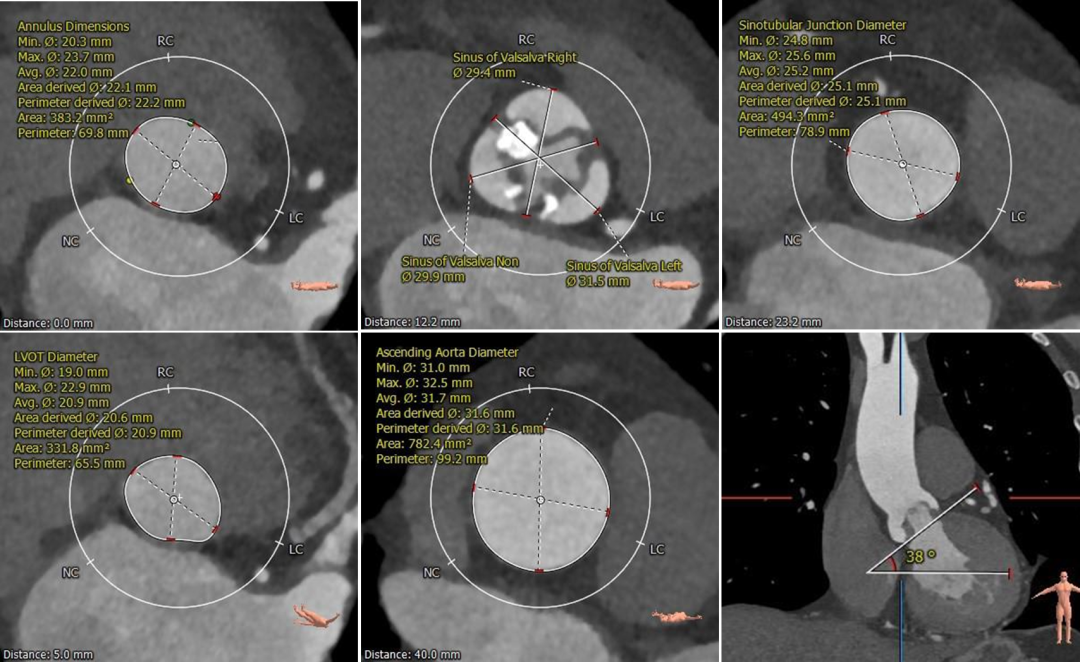

根部测量

瓣环平均径25.4mm,瓦氏窦、STJ、升主内径可,非横位心

瓣环平均径22.2mm,瓦氏窦、STJ、升主内径略小,非横位心